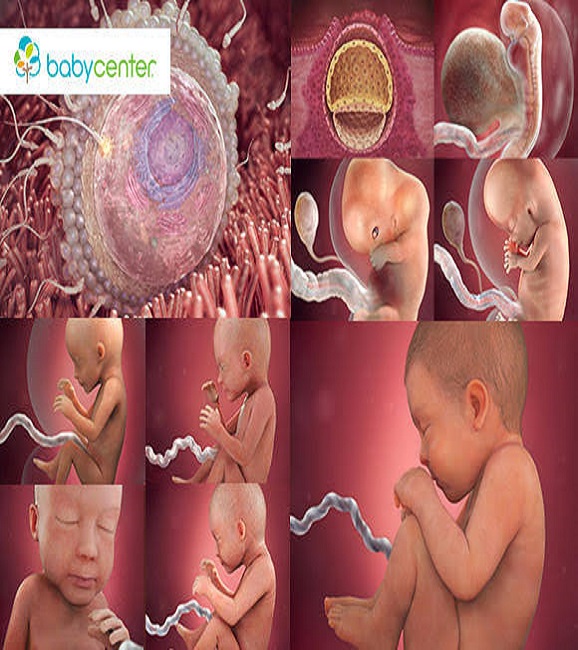

delivery. Most of us know where embryos begin their life. They start in the mother's womb. After spending around nine months, inside

Two tiny parts are needed to make a baby. They are too small to be seen well without a microscope. One part is called

the sperm cell. It comes from the father. The second part is the egg cell. It is made by the mother's body. Children are made

If we could see a sperm cell, it would look like a tiny tadpole. It has a small tail and swims quickly.

The sperm wants to find an egg and begin a baby. However, of the billions of sperm not many match up with the egg.

When these two cells come together, they fertilize. This means the tiny parts have started to make life. The two cells grows by

splitting and still staying together. the two become four, the four becomes sixteen.

They keep splitting for eight days and yet it is

only a small speck. You could put fifty of these on one inch of a ruler. When it is this size, the cells rest against the mother's womb.

There it will grow and live until it is time to be born.

The minutes these two cells meet most of the child's looks are put together. It hair, colour, sex, face and more are all settled.

As the cells grow they form three layers. The outside layer forms the skin. The middle layer makes the skeleton and nervous system.

The third layer will create our digestive tract.